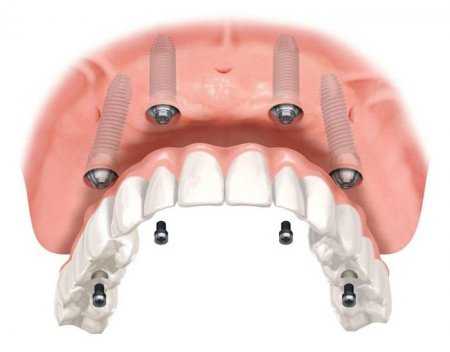

Титан имеет большую популярность в медицине: любят его ортопеды, кардиологи, стоматологи и даже нейрохирурги. Из титановых сплавов изготавливают легкие и долговечные хирургические инструменты.

В современном мире люди живут долгой активной жизнью. Но очень часто получают повреждения, например, в результате занятий спортом или в автомобильных авариях и происшествиях. И тут на помощь людям приходит металл будущего. Одним из ценных свойств титана является его биологическая совместимость с живой тканью. Титан и его сплавы (например, ВТ6 и ВТ14) является идеальным материалом для протезирования. Медики называют это свойство — «настоящее родство». Сочетание высокой удельной прочности и практически идеальной совместимости титана и его сплавов с тканями человеческого организма делает его максимально эффективным материалом для изготовления протезов, имплантантов, зубных металлокерамических коронок и каркасов мостовидных протезов. Титановые элементы совершенно безопасны для костей и мышц. Они не вызывают аллергию, не разрушаются при взаимодействии с жидкостями и тканями организма и, конечно, с медицинскими препаратами. Кроме этого, протезы, изготовленные из титановых сплавов, очень прочны и износоустойчивы, хотя все время выдерживают большие нагрузки.

Из титана изготавливают протезы маленьких косточек внутри уха, благодаря чему к людям возвращается слух. Кардиологи в своей работе используют такие приборы, как электронный стимулятор и дефибриллятор, корпуса которых тоже изготовлены из титана.